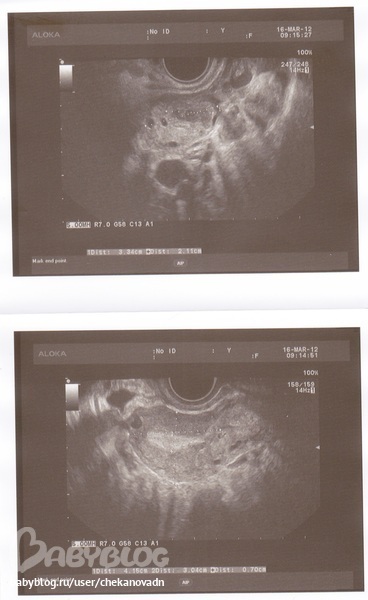

УЗИ малого таза

ФолликулометрияПланирую беременность, ходила на УЗИ сегодня (23 день цикла). Вопрос был по поводу рубца на матке (10 месяцев назад было кесарево), сказали все хорошо. Вот заключение, прокомментируйте, пожалуйста!

P.S.: В правом яичнике желтое тело - это значит, что была овуляция?? Если честно ниче в этом не понимаю

Привет. В заключении же все ок! Паталогии не выявлено. Желтое тело - это нормально, говорит о том что была овуляция, созревшая клеточка. При месячных все очистится.